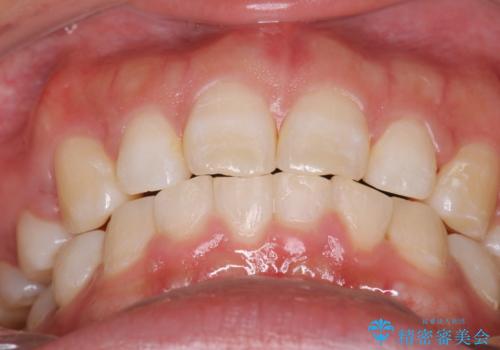

抜歯をすることでしっかり前歯を後方に移動させて、引っ込めることができました。

下の歯並びに対して、上の歯が全体的に前方に位置している状態でした。

上の歯の前から4番目の歯を2本抜歯して、そのスペースに前歯を移動させて、前歯を引っ込める計画としました。